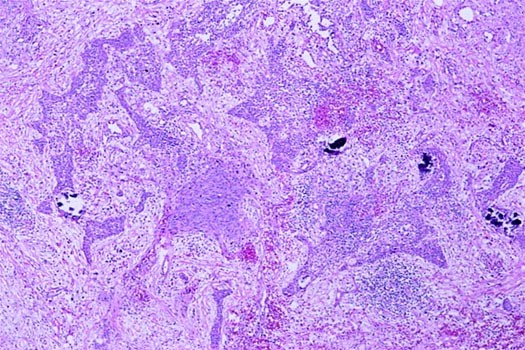

The primary histologic features and immunohistochemical staining results of the cases are presented in Table 2. In all cases, tumor foci were peripheral, multiple, and generally formed nodules. Peripheral lung septae or the subpleural interstitium were involved in all cases (Fig. 1). Tumor extended into surrounding pulmonary alveoli to varying degrees. Lymphangitic spread, when present, usually, but not exclusively, involved septal lymphatics and vessels (Fig. 4A). Circumferential growth around small vessels and bronchioles was noted in seven cases (32%; Fig. 4B). This growth pattern often resulted in tumor thrombi or bronchiole obstruction when tumor penetrated through the walls of the structure. Vasoformative regions were identified in 15 cases (71%). These regions consisted of anastomosing channels lined by mildly to markedly atypical tumor cells. These channels often contained red blood cells (Figs. 3, A–B, and 5A). Solid growth occurred in 17 cases (77%; Fig. 2). Fresh hemorrhage, clusters of siderophages, and extracellular hemosiderin deposition occurred both within tumor nodules and in immediately adjacent lung parenchyma (Fig. 5B).

Benign entities were considered because the metastatic foci disclosed one or more of the following features at low to intermediate power: a wedge-shaped, subpleural mass that was fibrotic and/or hemorrhagic, an intra-alveolar proliferation of spindle cells with fibrosis and inflammation, intra-alveolar acute hemorrhage with siderophages, and intravascular deposits of spindle cells and fibrin. At high power, however, neovascularization formed by cytologically atypical cells, solid growth, intravascular deposits containing atypical cells, or invasive growth by atypical cells could be appreciated. The degree of cytologic atypia and/or invasive growth thus precluded diagnosis of a benign entity. In particular, the presence of malignant vessel formation and the marked degree of cytologic atypia excluded Kaposi's sarcoma and epithelioid hemangioendothelioma, whereas immunohistochemical staining results confirming the endothelial nature of the malignant cells excluded the other malignancies in the differential.